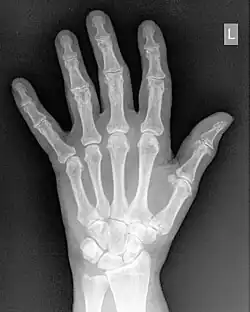

Histogram Processing

- Contrast enhancement can also be effected through manipulation of the image's statistical histogram and is illustrated in Figure 5.8. A histogram is a plot of the frequency of occurrence of each pixel value in an image - see panel (a) for an example, where this frequency is plotted as a function of pixel value. It can be seen that pixels from the black surroundings of the hand are indicated by the peak at low pixel values. It can also be seen that the pixel values representing bone and tissue attenuation form a broad range of lower frequencies extending to just over half the grey scale. Indeed the pixels of the 'L' marker can be seen to form an isolated blip at a pixel value of 75. Note that the term frequency as used here should not be confused with the term spatial frequency we have been using in our discussion of Fourier techniques.

- Manipulating such histogram data can be used for contrast enhancement by redistributing the pixel values to generate, for instance, a better utilisation of the grey scale. The process of Histogram Equalisation is illustrated in the Figure 5.8, panel (b) along with its histogram - panel (c). It can be seen that the process broadens the frequency distribution so that it now spans the full range of the grey scale. Notice also that the process can generate absent pixel values.:Manipulating such histogram data can be used for contrast enhancement by redistributing the pixel values to generate, for instance, a better utilisation of the grey scale. The process of Histogram Equalisation is illustrated in the Figure 5.8, panel (b) along with its histogram - panel (c). It can be seen that the process broadens the frequency distribution so that it now spans the full range of the grey scale. Notice also that the process can generate absent pixel values.